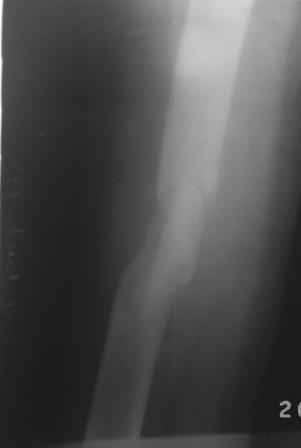

Добрый вечер, уважаемые коллеги.Произведена операция БИОС. Больной 35л, 3-месяца назад получил тяжелую сочетанную травму, после улучшение состояния доставлен к нам, Р-грамма прилагается.

Учитывая поворот большого костного осколка на 180гр. , произведена открытая репозиция, скелетирована только передне-наружная поверхность., антеградный и/м остеосинтез, и наш старенький ЭОП перестал работать, пришлось дистальную блокировку произвести в рентген кабинете под сериоскоп-Сименс, с большими трудностями.

И в конце выяснилось что имеется диастаз задне-внутренной стенки. Заново блокировать рентгенологи не разрешили.